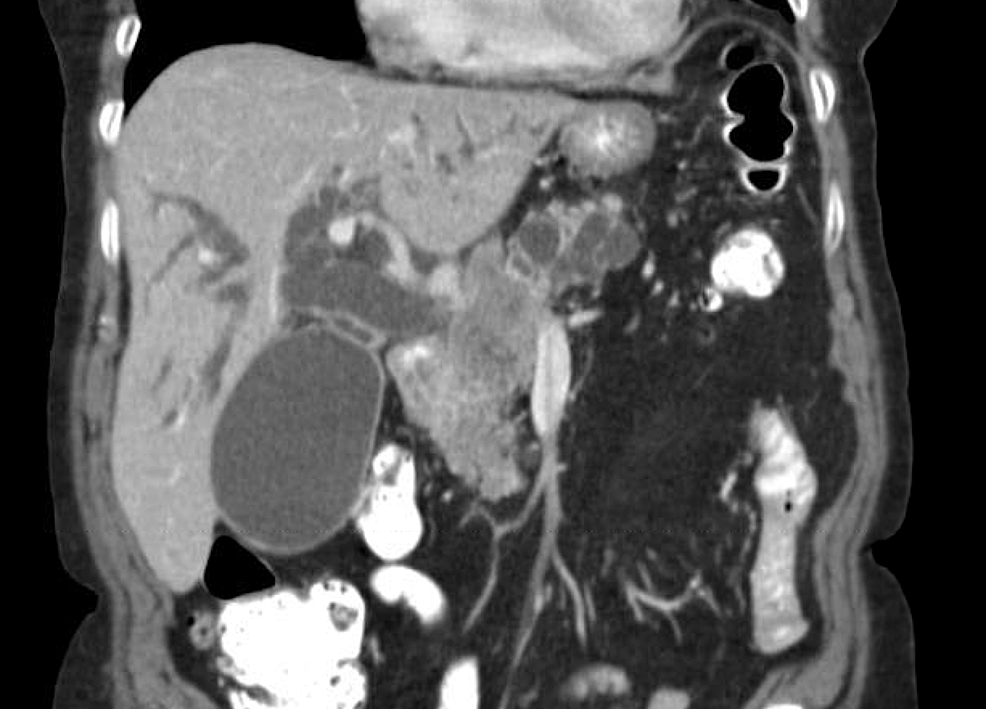

Squamous cell carcinoma of the skin. Wasserman, md ●adrian m 1from the department of radiology, university of minnesota, minnesota veterans administration mous cell carcinoma (1). Squamous cell carcinoma accounts for only 3 to 7% of bladder cancers in western countries, but in certain countries where parasites are very common (especially schistosomiasis) it is found much more frequently.

Squamous cell carcinoma of the urinary bladder is a malignant neoplasm derived from bladder urothelium with pure squamous phenotype.

Which can arise from a urachal remnant? Squamous cell carcinoma of the urinary bladder is a malignant neoplasm derived from bladder urothelium with pure squamous phenotype. It is associated with keratinizing squamous metaplasia. The diagnosis of squamous cell carcinoma of the bladder should be reserved for those tumors that are predominantly keratin forming.